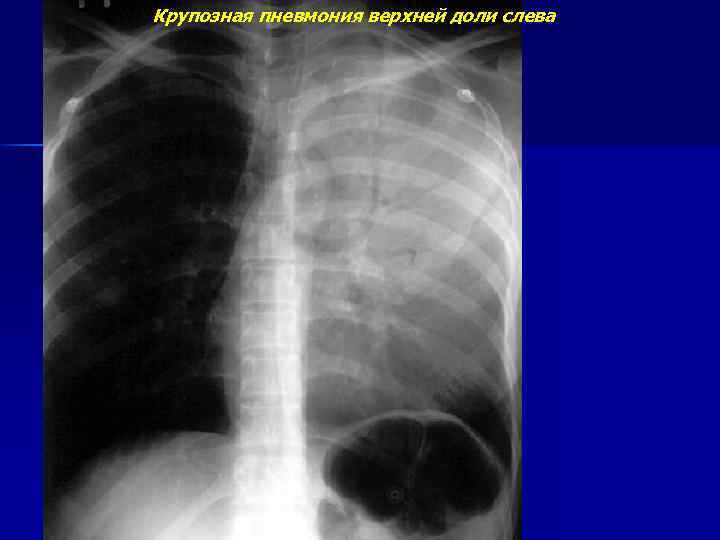

Крупозная пневмония верхней доли слева

Крупозная пневмония верхней доли слева (продолжение)